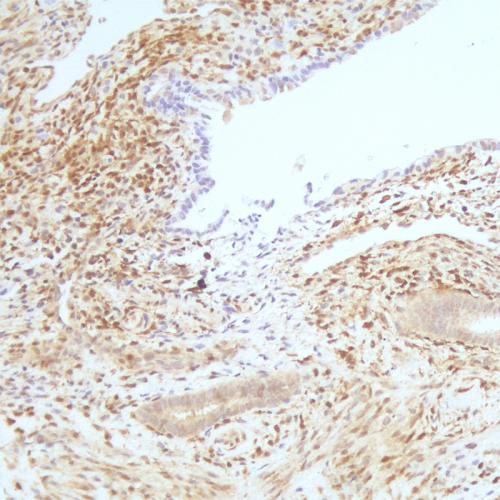

我國(guó)胃癌發(fā)病率居惡性腫瘤第2位,新發(fā)病例68萬(wàn)例,死亡49萬(wàn)例。研究表明:HP感染者均會(huì)引起慢性活動(dòng)性胃炎,在胃黏膜萎縮和腸化生的發(fā)生和發(fā)展中也起重要作用[1],HP感染和胃癌的發(fā)生密切相關(guān),根除HP是預(yù)防胃癌的有效措施。IHC染色特異性強(qiáng)、靈敏度高、陽(yáng)性準(zhǔn)確性高、易于判讀,便于各級(jí)醫(yī)院病理科開(kāi)展業(yè)務(wù),特別適合胃鏡活檢標(biāo)本量較大的情況,值得推廣[2-3]。